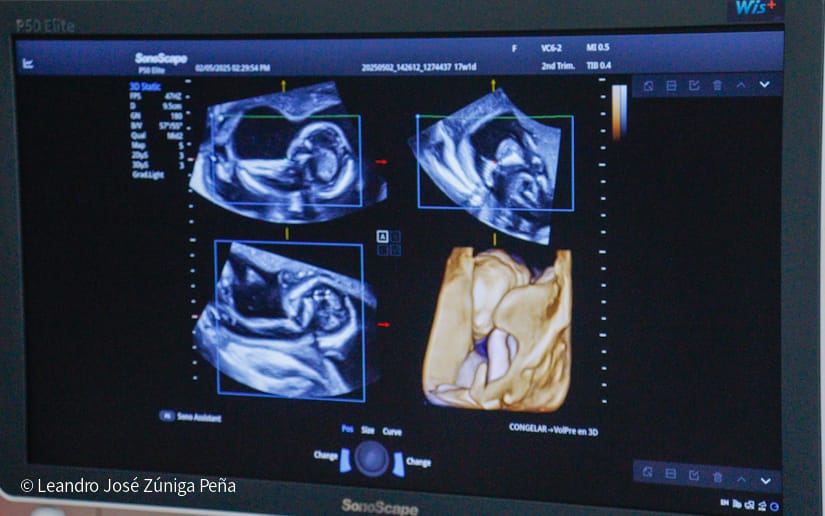

“Con estos ultrasonidos, que son de alta tecnología en el país, estamos completando 32 equipos de ultrasonido que están ubicados en las diferentes unidades de salud. Estos últimos 6 equipos nos van a permitir hacer diagnóstico de manera preventiva a la mujer embarazada, tenemos recursos humanos calificados, médicos especialistas formados por nuestro gobierno, en nuestro país, que tienen todos los conocimientos necesarios para poder hacer diagnóstico de anomalías congénitas, diagnóstico prenatal de alteraciones en la embarazada y en el feto y poder hacer prevención de la preclancia, el parto prematuro, la restricción del crecimiento fetal o bajo peso, que son morbilidades que afectan a nuestras embarazadas y a nuestro recién nacido, de igual manera, la tecnología volumétrica que se ha adquirido en estos equipos como el 3D y el 4D permite obtener mejores imágenes de anomalías congénitas para que estas pacientes que son captadas en estas unidades puedan ser referidas al Bertha Calderón”, explicó el especialista.